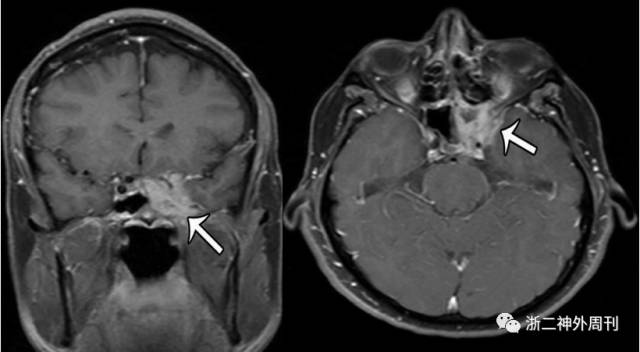

多数颅内IMT在CT上呈高密度病变,约有超过4/5伴有骨质破坏。MRI显示颅内IMT在T1像上呈等信号,T2像呈低信号,增强像上伴有强化,尤其当IMT位于海绵窦内时强化更为明显(图5)。

图5. 典型海绵窦IMT的影像学表现(箭头所指为IMT病变)